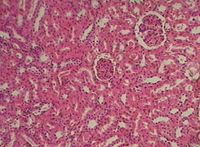

Гистологический срез почки: изучаем микроструктуру